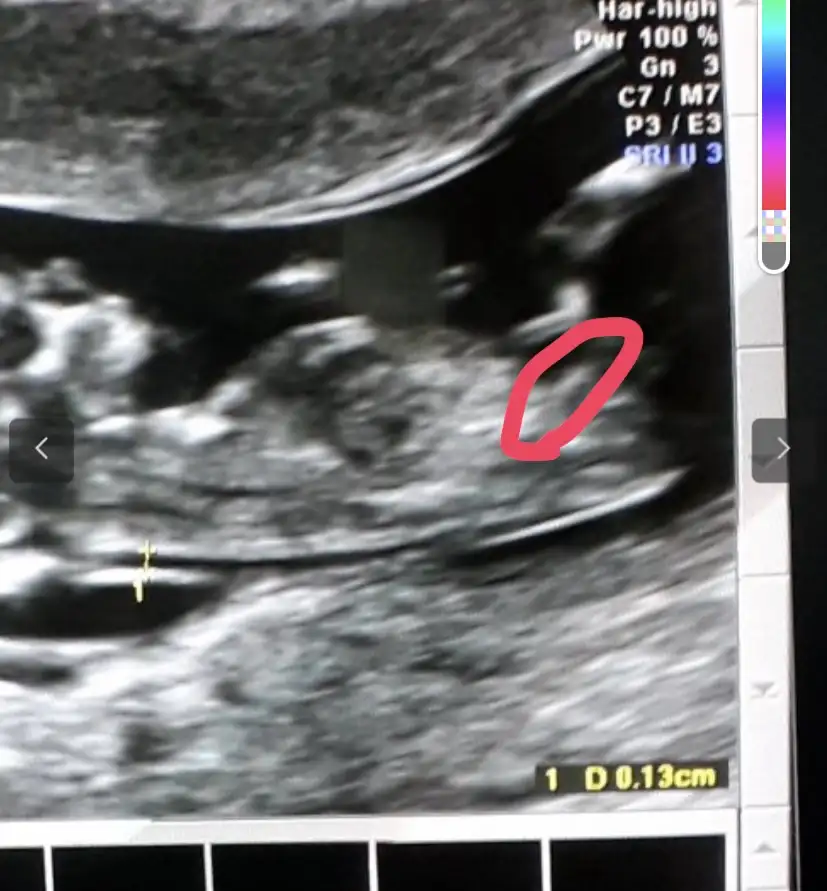

O çıkıntı kızdada mı var ne çıkıntısı ki oEki Görüntüle 2846176

Kızlar tam olarak buben kızımdayken bilmiyordum fakat geriye dönük ultrason goruntusune baktım gecen nub tutmus :)

Bende o çıkıntıyı erkek dedim hemen kuyruk sokumu o zamanNe oldugunu bilmiyorım canımkızdaykı ile erkegın acısı farklı işte